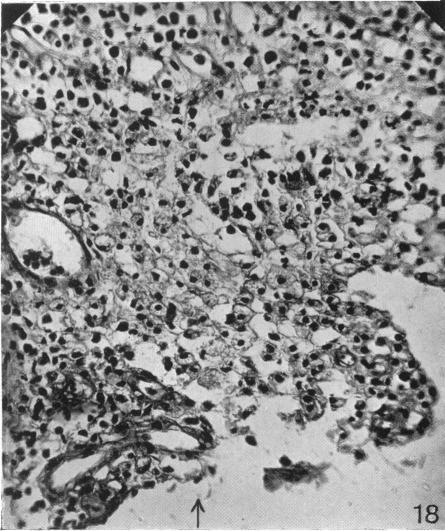

The So-called Interscapular Gland and Tumours Arising Therein.

J Anat. 1927 Jul;61(Pt 4):452-466.11.